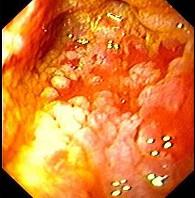

男性,67岁,反复上腹饱胀不适2年,以餐后为甚,伴反酸、嗳气、食欲不振、恶心、呕吐等。胃镜检查胃窦粘膜见散在灰白色斑块,如图:该病人最可能的诊断是 ( )...

问题 男性,67岁,反复上腹饱胀不适2年,以餐后为甚,伴反酸、嗳气、食欲不振、恶心、呕吐等。胃镜检查胃窦粘膜见散在灰白色斑块,如图:该病人最可能的诊断是 ( )

选项 A.胃黄斑瘤 B.慢性浅表性胃炎 C.慢性萎缩性胃炎伴肠上皮化生 D.胃泌素瘤 E.消化性溃疡

答案 C